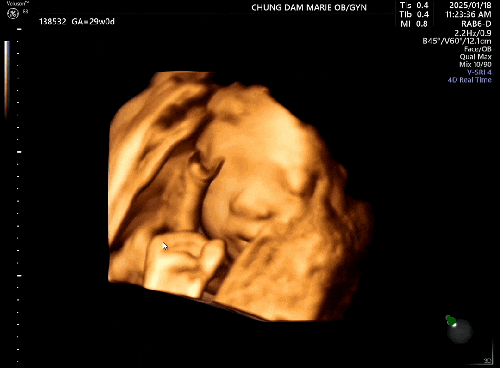

임신기록 : 시험관 임신 29주차, 입체초음파로 만난 알콩이 - 3D 입체초음파와 4D 입체초음파 차이 #2차정밀초음파

25년 1월 18일 토요일 시험관 임신 29주차! * 이식일 : 24년 7월 17일 수요일 * 출산예정일 : 25년 4월 5일...